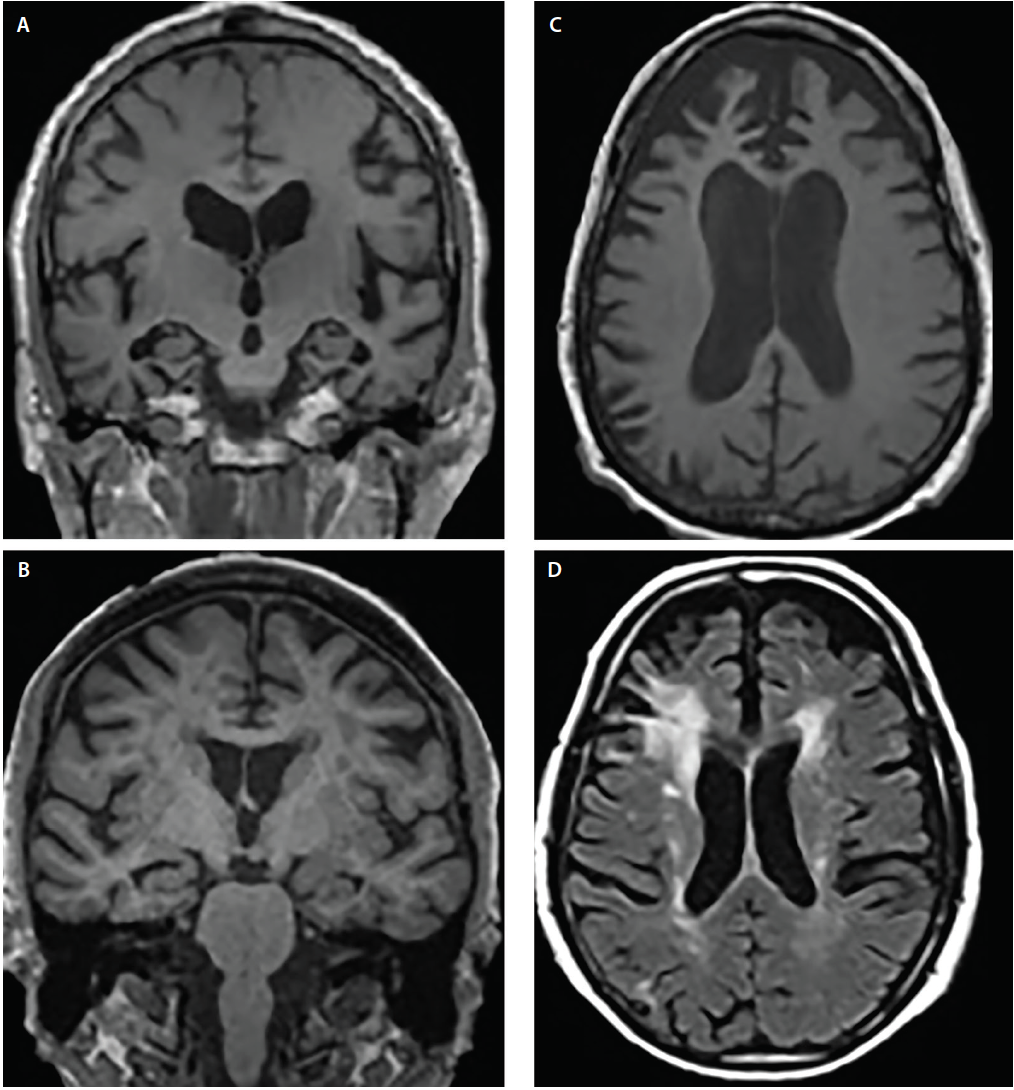

a An example brain CT of multi-infarct dementia. The brain CT showed …

Ct Scan Alzheimer’s Vs Normal – DementiaTalkClub.com

Vascular dementia – The Lancet

Using MRI scans to reveal early signs of dementia | Health-RI

Dementia brain ct hi-res stock photography and images – Alamy

Dementia brain ct hi-res stock photography and images – Alamy